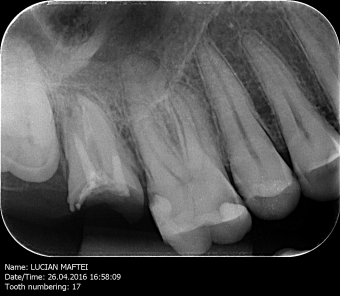

Radiologie dentară modernă realizată direct în clinică La Clinica ...